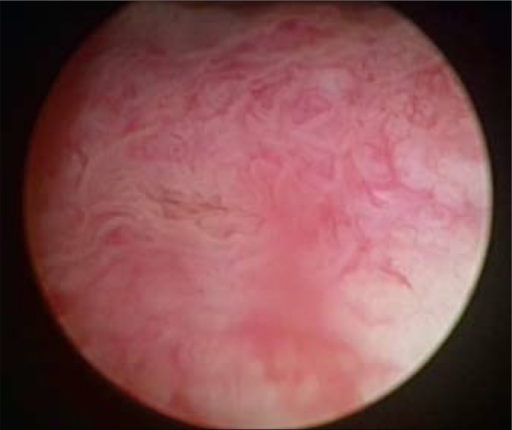

Cystoscopic image of polypoid urinary bladder tumor. Image courtesy of …

Cystoscopy (bladder mucosa). | Open-i

Cystoscopic findings in bladder tumors. (a) White light mode (left …